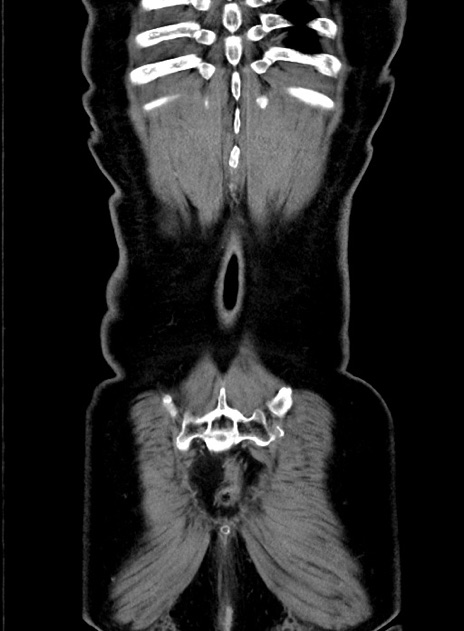

症例9(冠状断像)

【症例】 60歳代女性

【主訴】むかつき、みぞおちの痛み

【現病歴】3日前よりむかつきがあり、食事がとれない。

【既往歴】糖尿病

【身体所見】発熱なし、心窩部圧痛軽度あるも、腹膜刺激症状なし。

【データ】WBC 7400、CRP 1.92